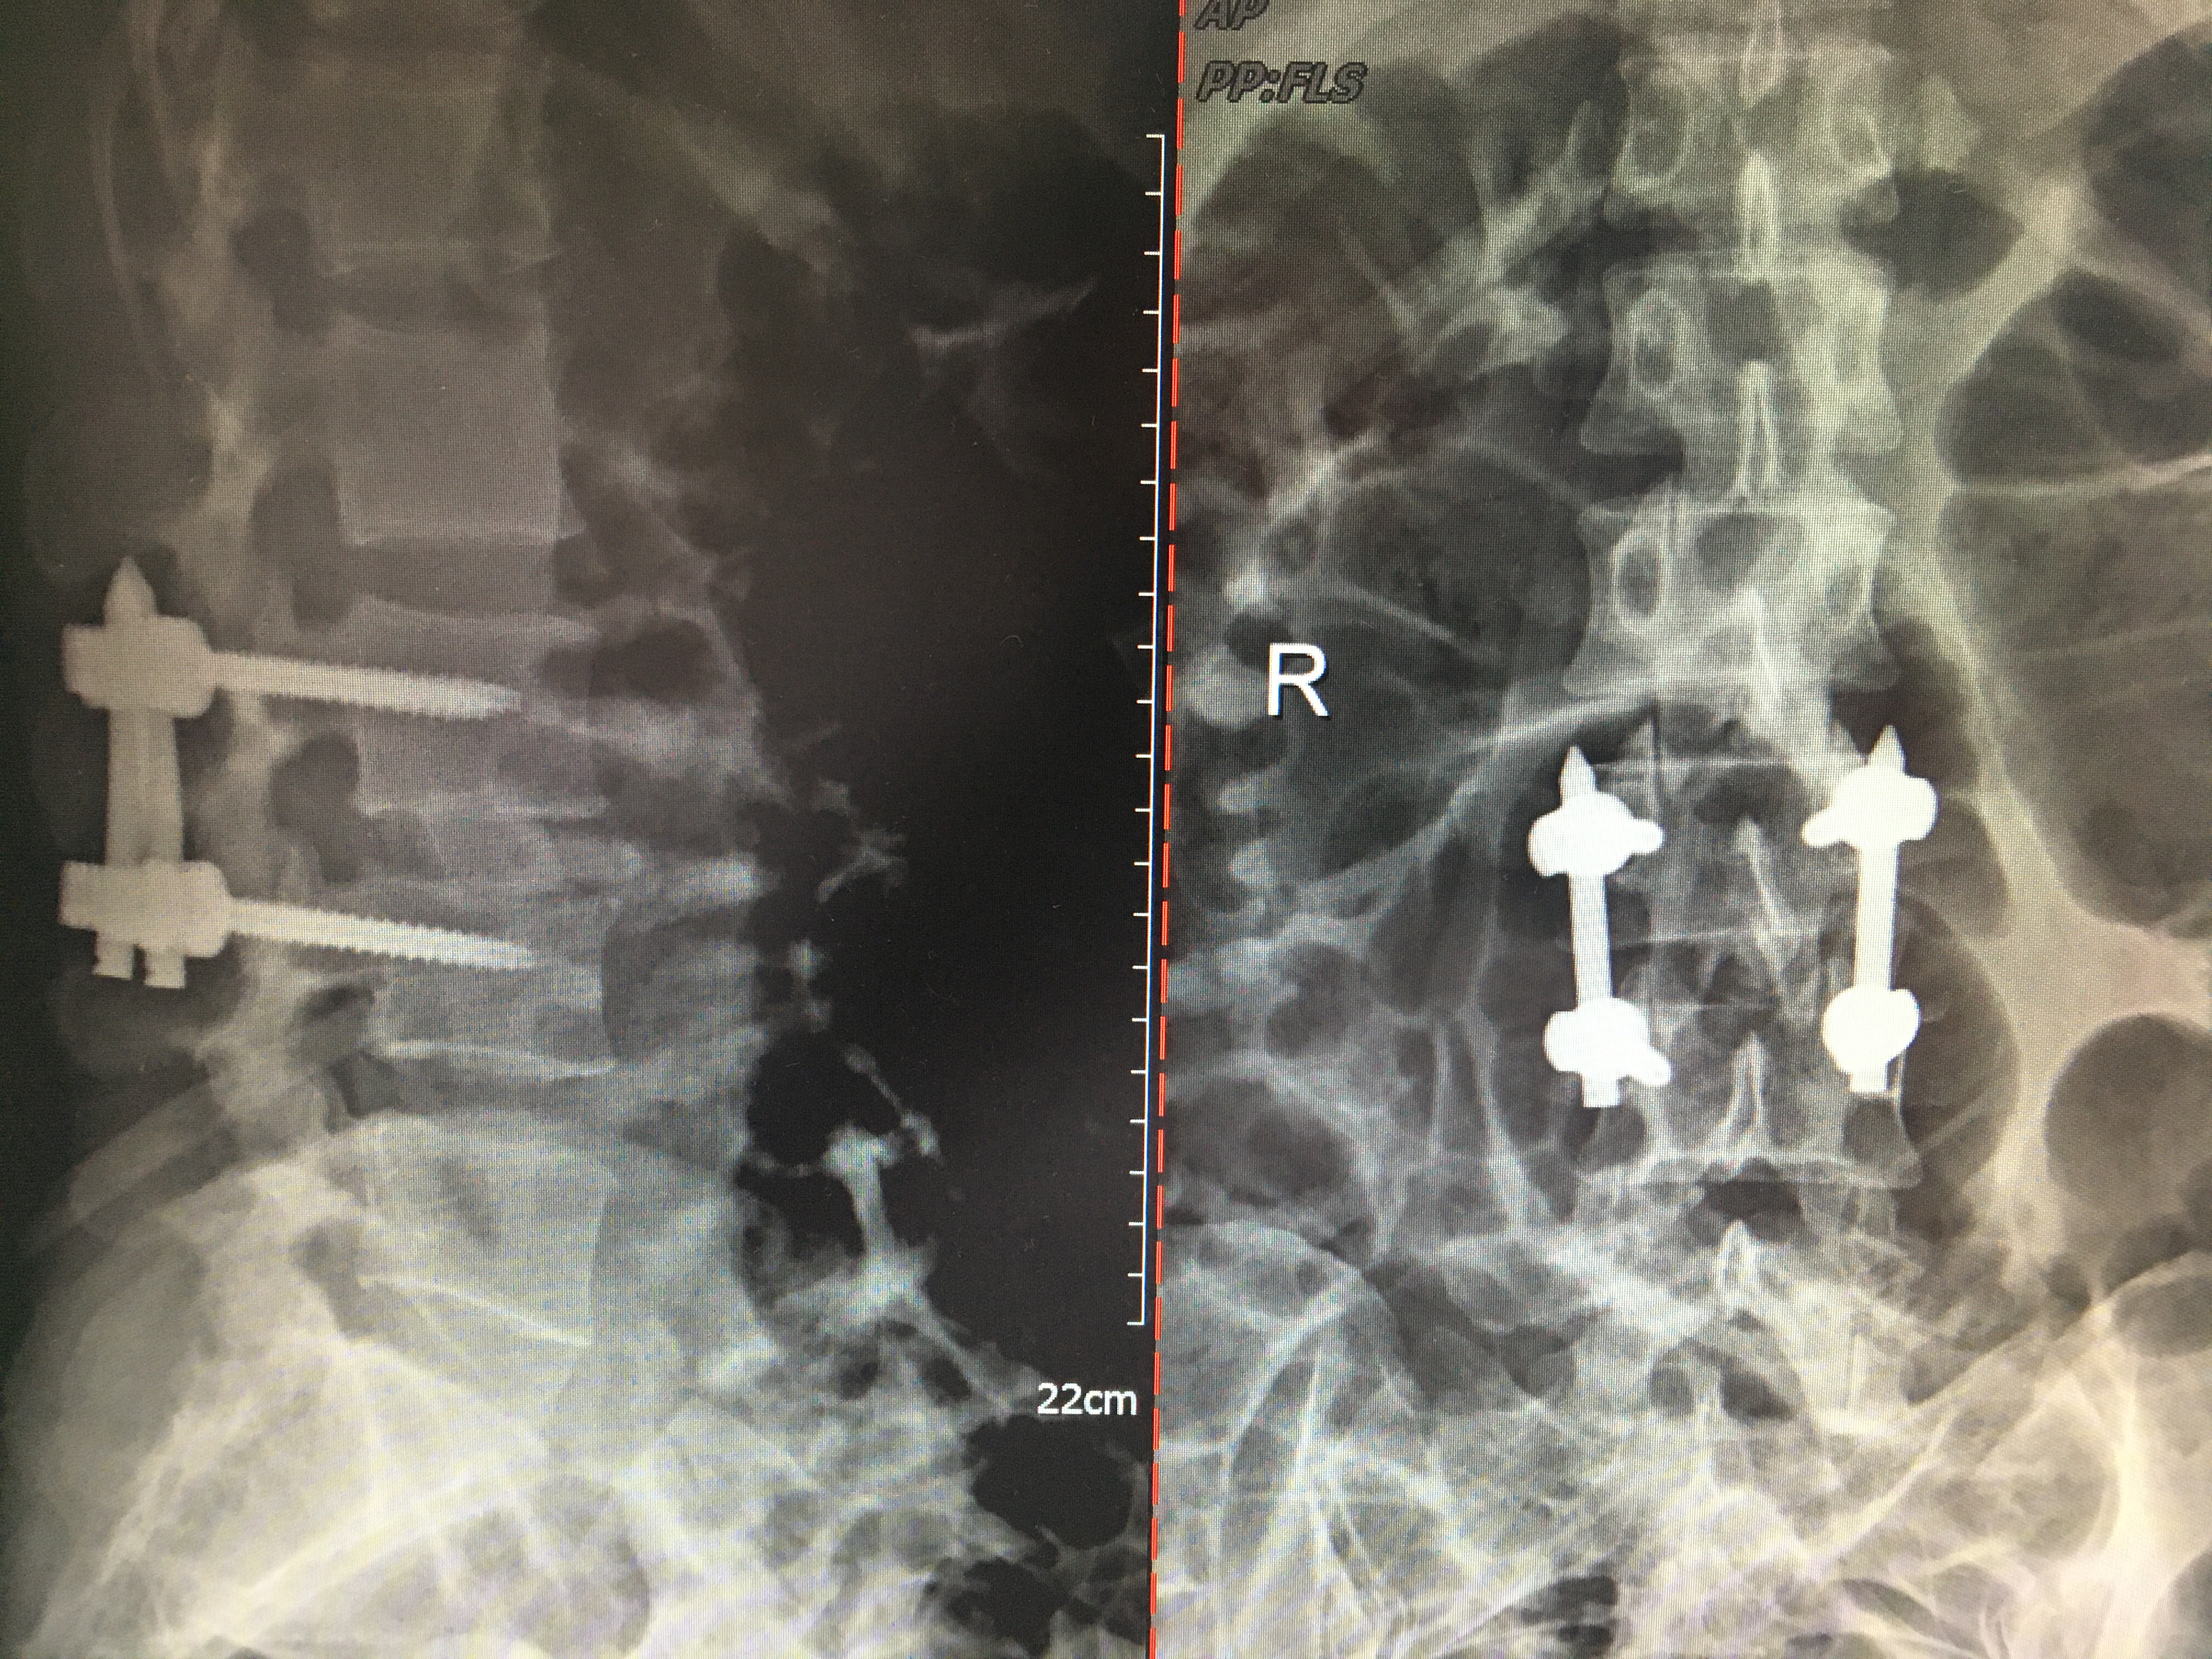

術(shù)后X線

術(shù)后第2天,陳姐能佩戴支具下地行走。根據(jù)術(shù)中提取的組織做涂片及培養(yǎng)后確定為化膿性脊柱炎(腰3-4):戈登鏈球菌感染。腰椎感染原因明確了,這下陳姐治療用藥終于有了科學(xué)依據(jù)。2周后,陳姐手術(shù)傷口愈合了,腰板變直了,人也變美了。